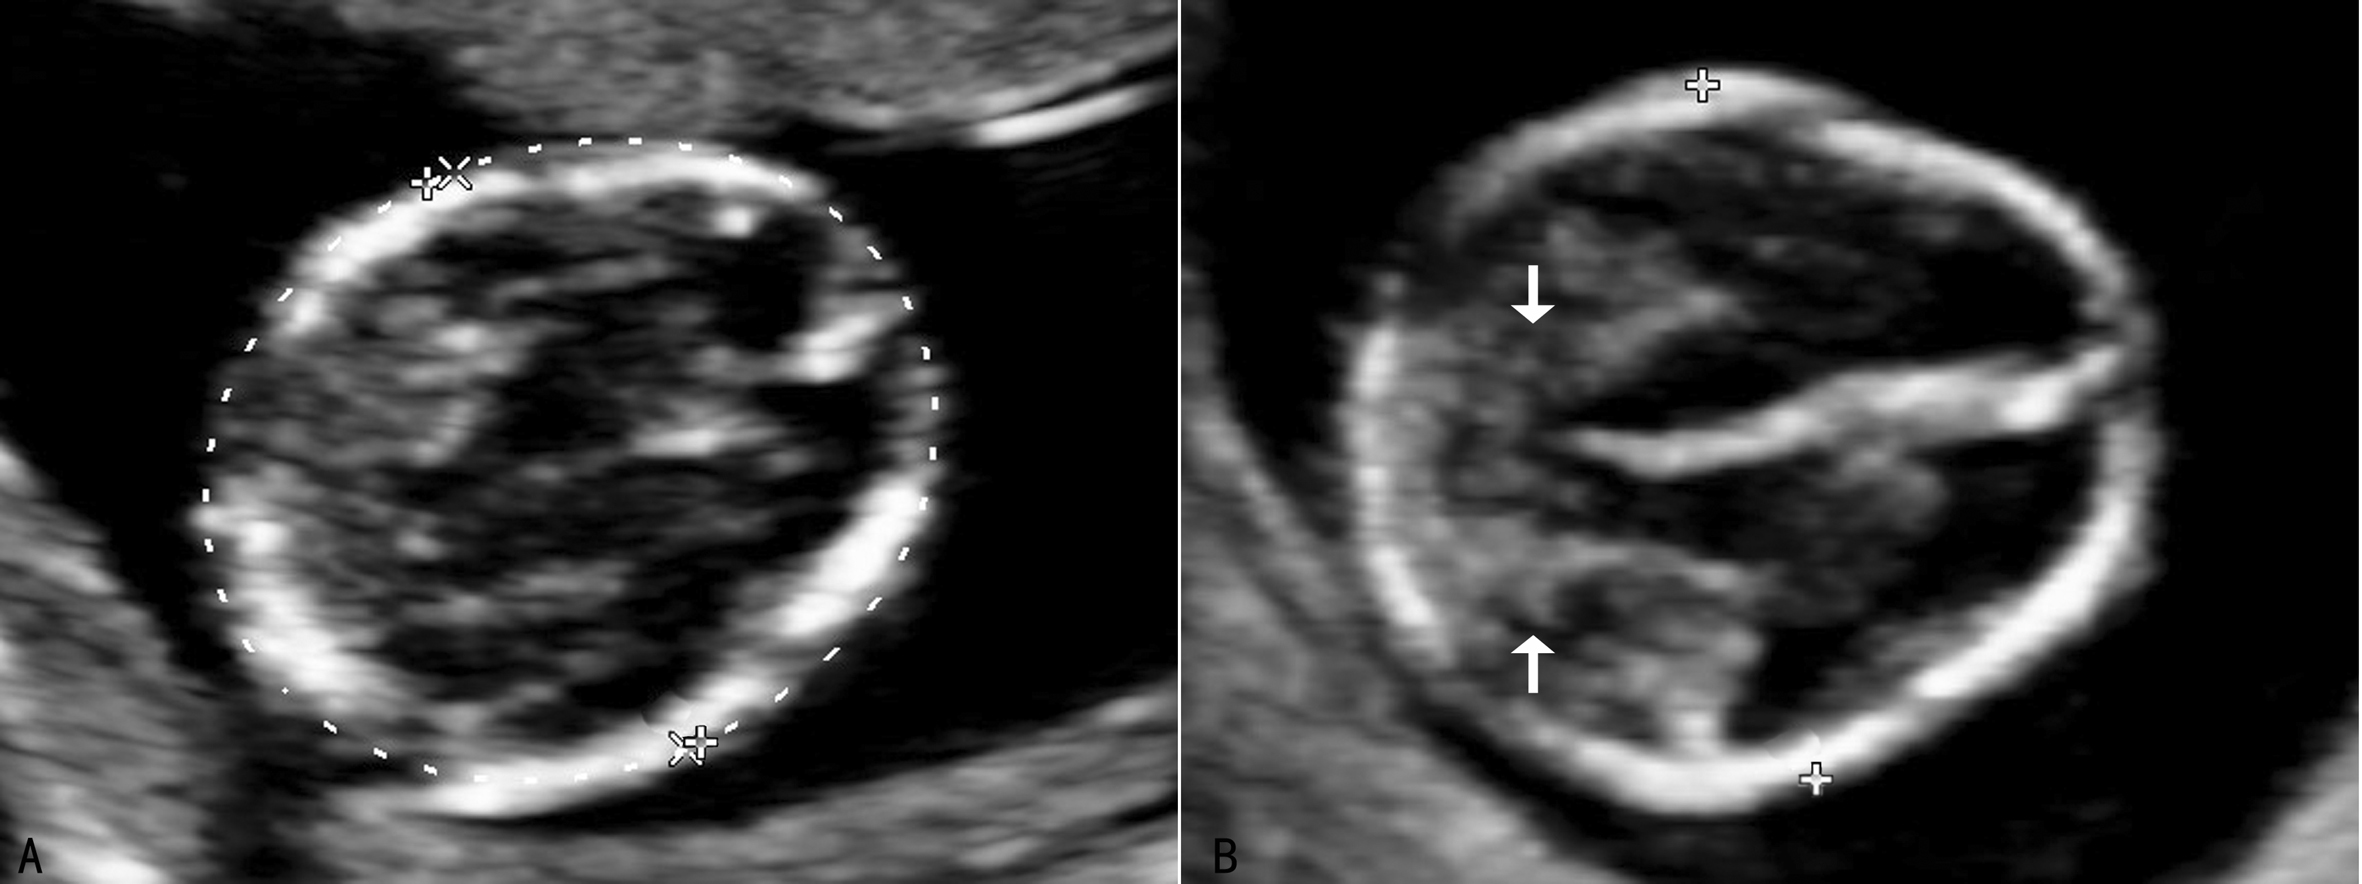

超声显像检查时需要观察矢状切面、横切面和冠状切面(图3,4)。矢状切面显示椎体及一侧椎弓的骨化中心呈现两条串珠状的平行线,在骶尾部收拢合并,因为一个切面只能显示一侧的椎弓,需动态扫描使两侧椎弓都能显示;[f2] 横切面的扫查需要耐心仔细从颈椎到骶尾部依次进行,不同的椎体超声表现不同,第一颈椎呈四边形或圆钝的三角形(图3A),其他呈现等腰三角形,尖端为椎体,指向胎儿腹侧(图3B,图4C、D)。冠状切面,声束靠近皮肤显示两排平行的骨化中心,是双侧椎弓,声束再向胎儿腹侧扫查,可显示一排椎体(图5),透明三维显示可以直观地显示胎儿脊柱的空间结构和形态(图6)。扫查时要注意覆盖在脊柱上的皮肤的完整性,以免遗漏微小的脊柱裂或者隐形脊柱裂,隐形脊柱裂有时仅表现为皮肤鼓起的小泡状无回声。

图3 颈椎的横断面(A)及胸椎横断面(B)

图4 腰椎横断面(C)及骶椎横断面(D)